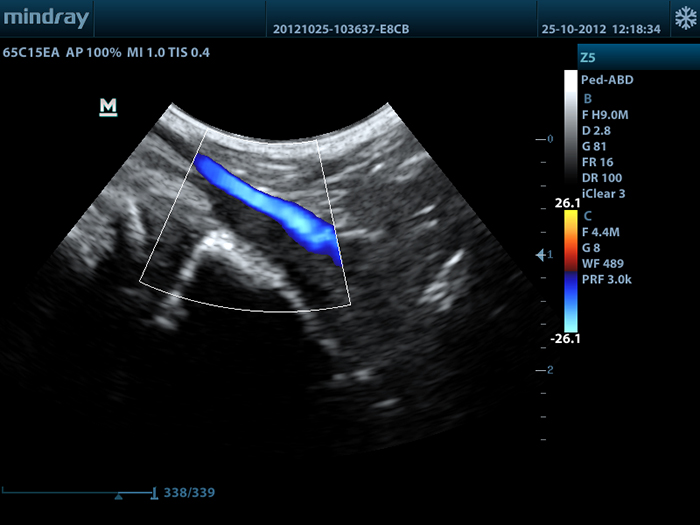

Mindray Z5 Vet